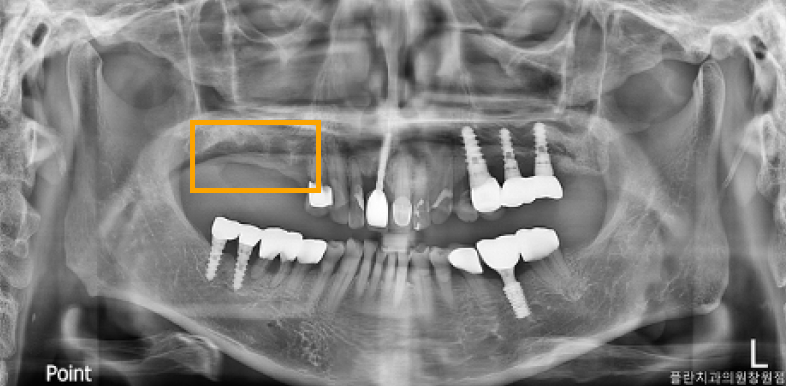

상악동 거상술이 무엇인가요?

윗니 위쪽에는 '상악동'이라는 비어있는

공기 주머니가 있습니다.

치아를 잃은 지 오래되면 이 주머니가 아래로

내려오고 잇몸 뼈는 얇아지게 됩니다.

마치 풍선처럼 얇은 상악동 막을 조심스럽게

들어 올리고, 그 빈 공간에 뼈를 채워 넣어

임플란트를 심을 수 있는 튼튼한 바탕을

만드는 것이 바로 상악동 거상술입니다.